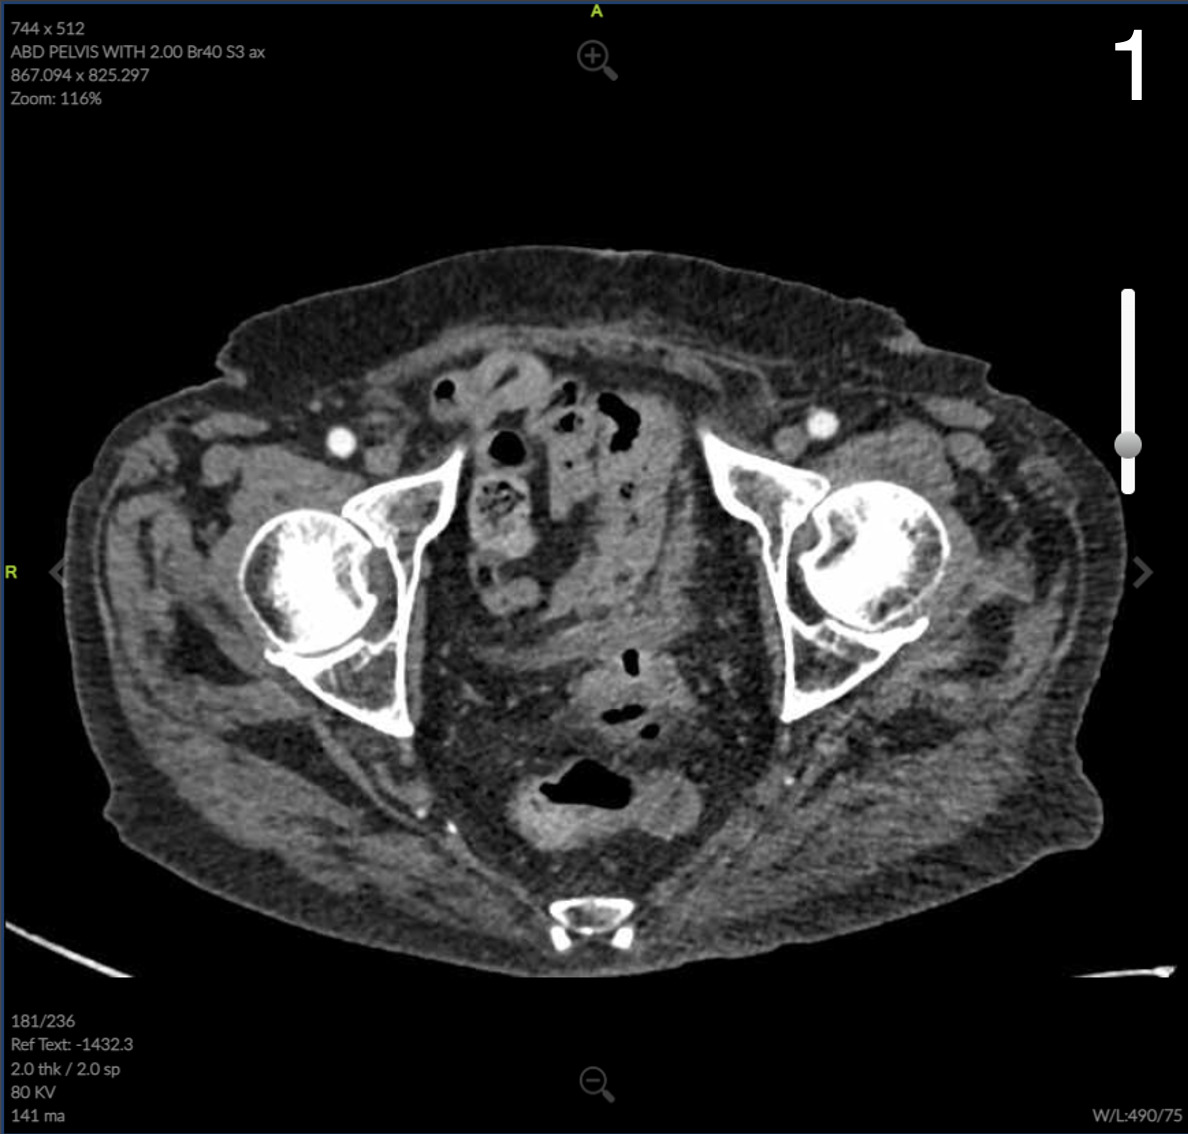

Computed Tomography (CT) of the abdomen and pelvis showed colonic wall thickening particularly in the pelvis close to the vaginal vault. A colonoscopy revealed a severe kink that could not be crossed in the sigmoid colon and extensive diverticular disease.